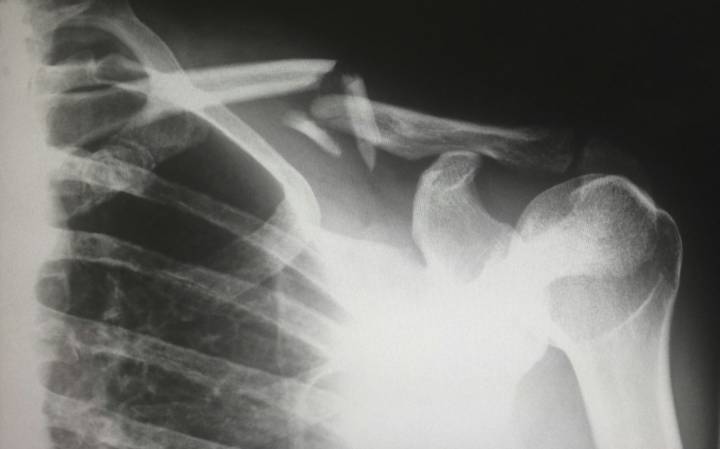

La Artroscopía de Hombro es una Técnica Quirúrgica Mínimamente Invasiva que permite diagnosticar y tratar diversas lesiones articulares mediante pequeñas incisiones.